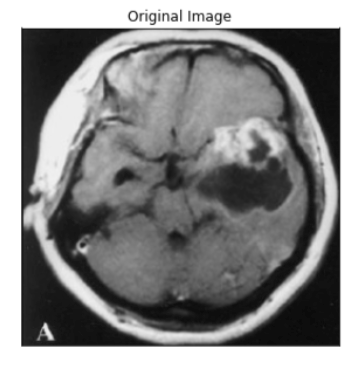

Test your model prediction on the validation set:

#Validation set

ind = 9

display_image(dataset_val, ind)

predict_and_plot_differences(dataset_val, ind)